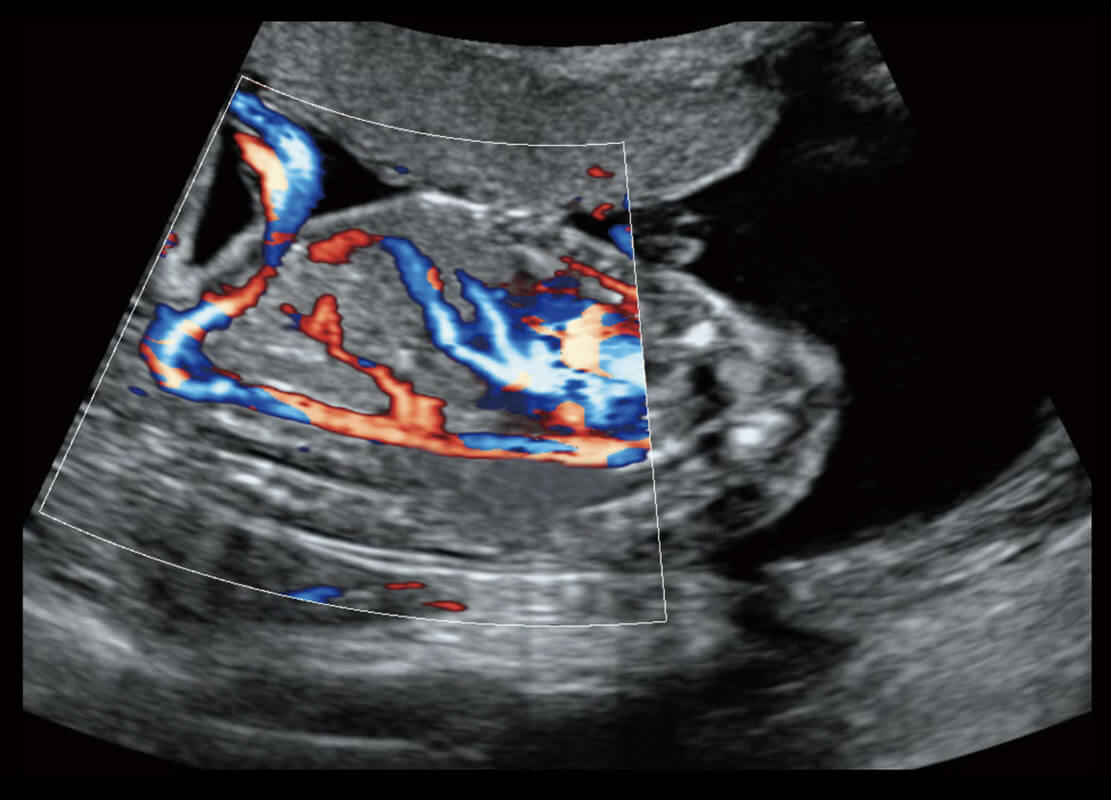

• 胎儿体循环

P60搭载一系列胎儿心脏成像技术,实现精细的胎儿心脏评估。

• 四腔心血流